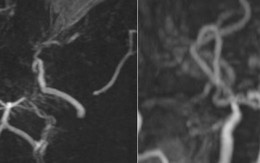

Hình ảnh MRI khiến bác sĩ bất ngờ: Mạch máu não bệnh nhân mờ như "khói thuốc"

Kết quả chụp MRI của 1 bệnh nhân bị đau đầu cho thấy mạch máu não của bệnh nhân mờ như "khói thuốc".